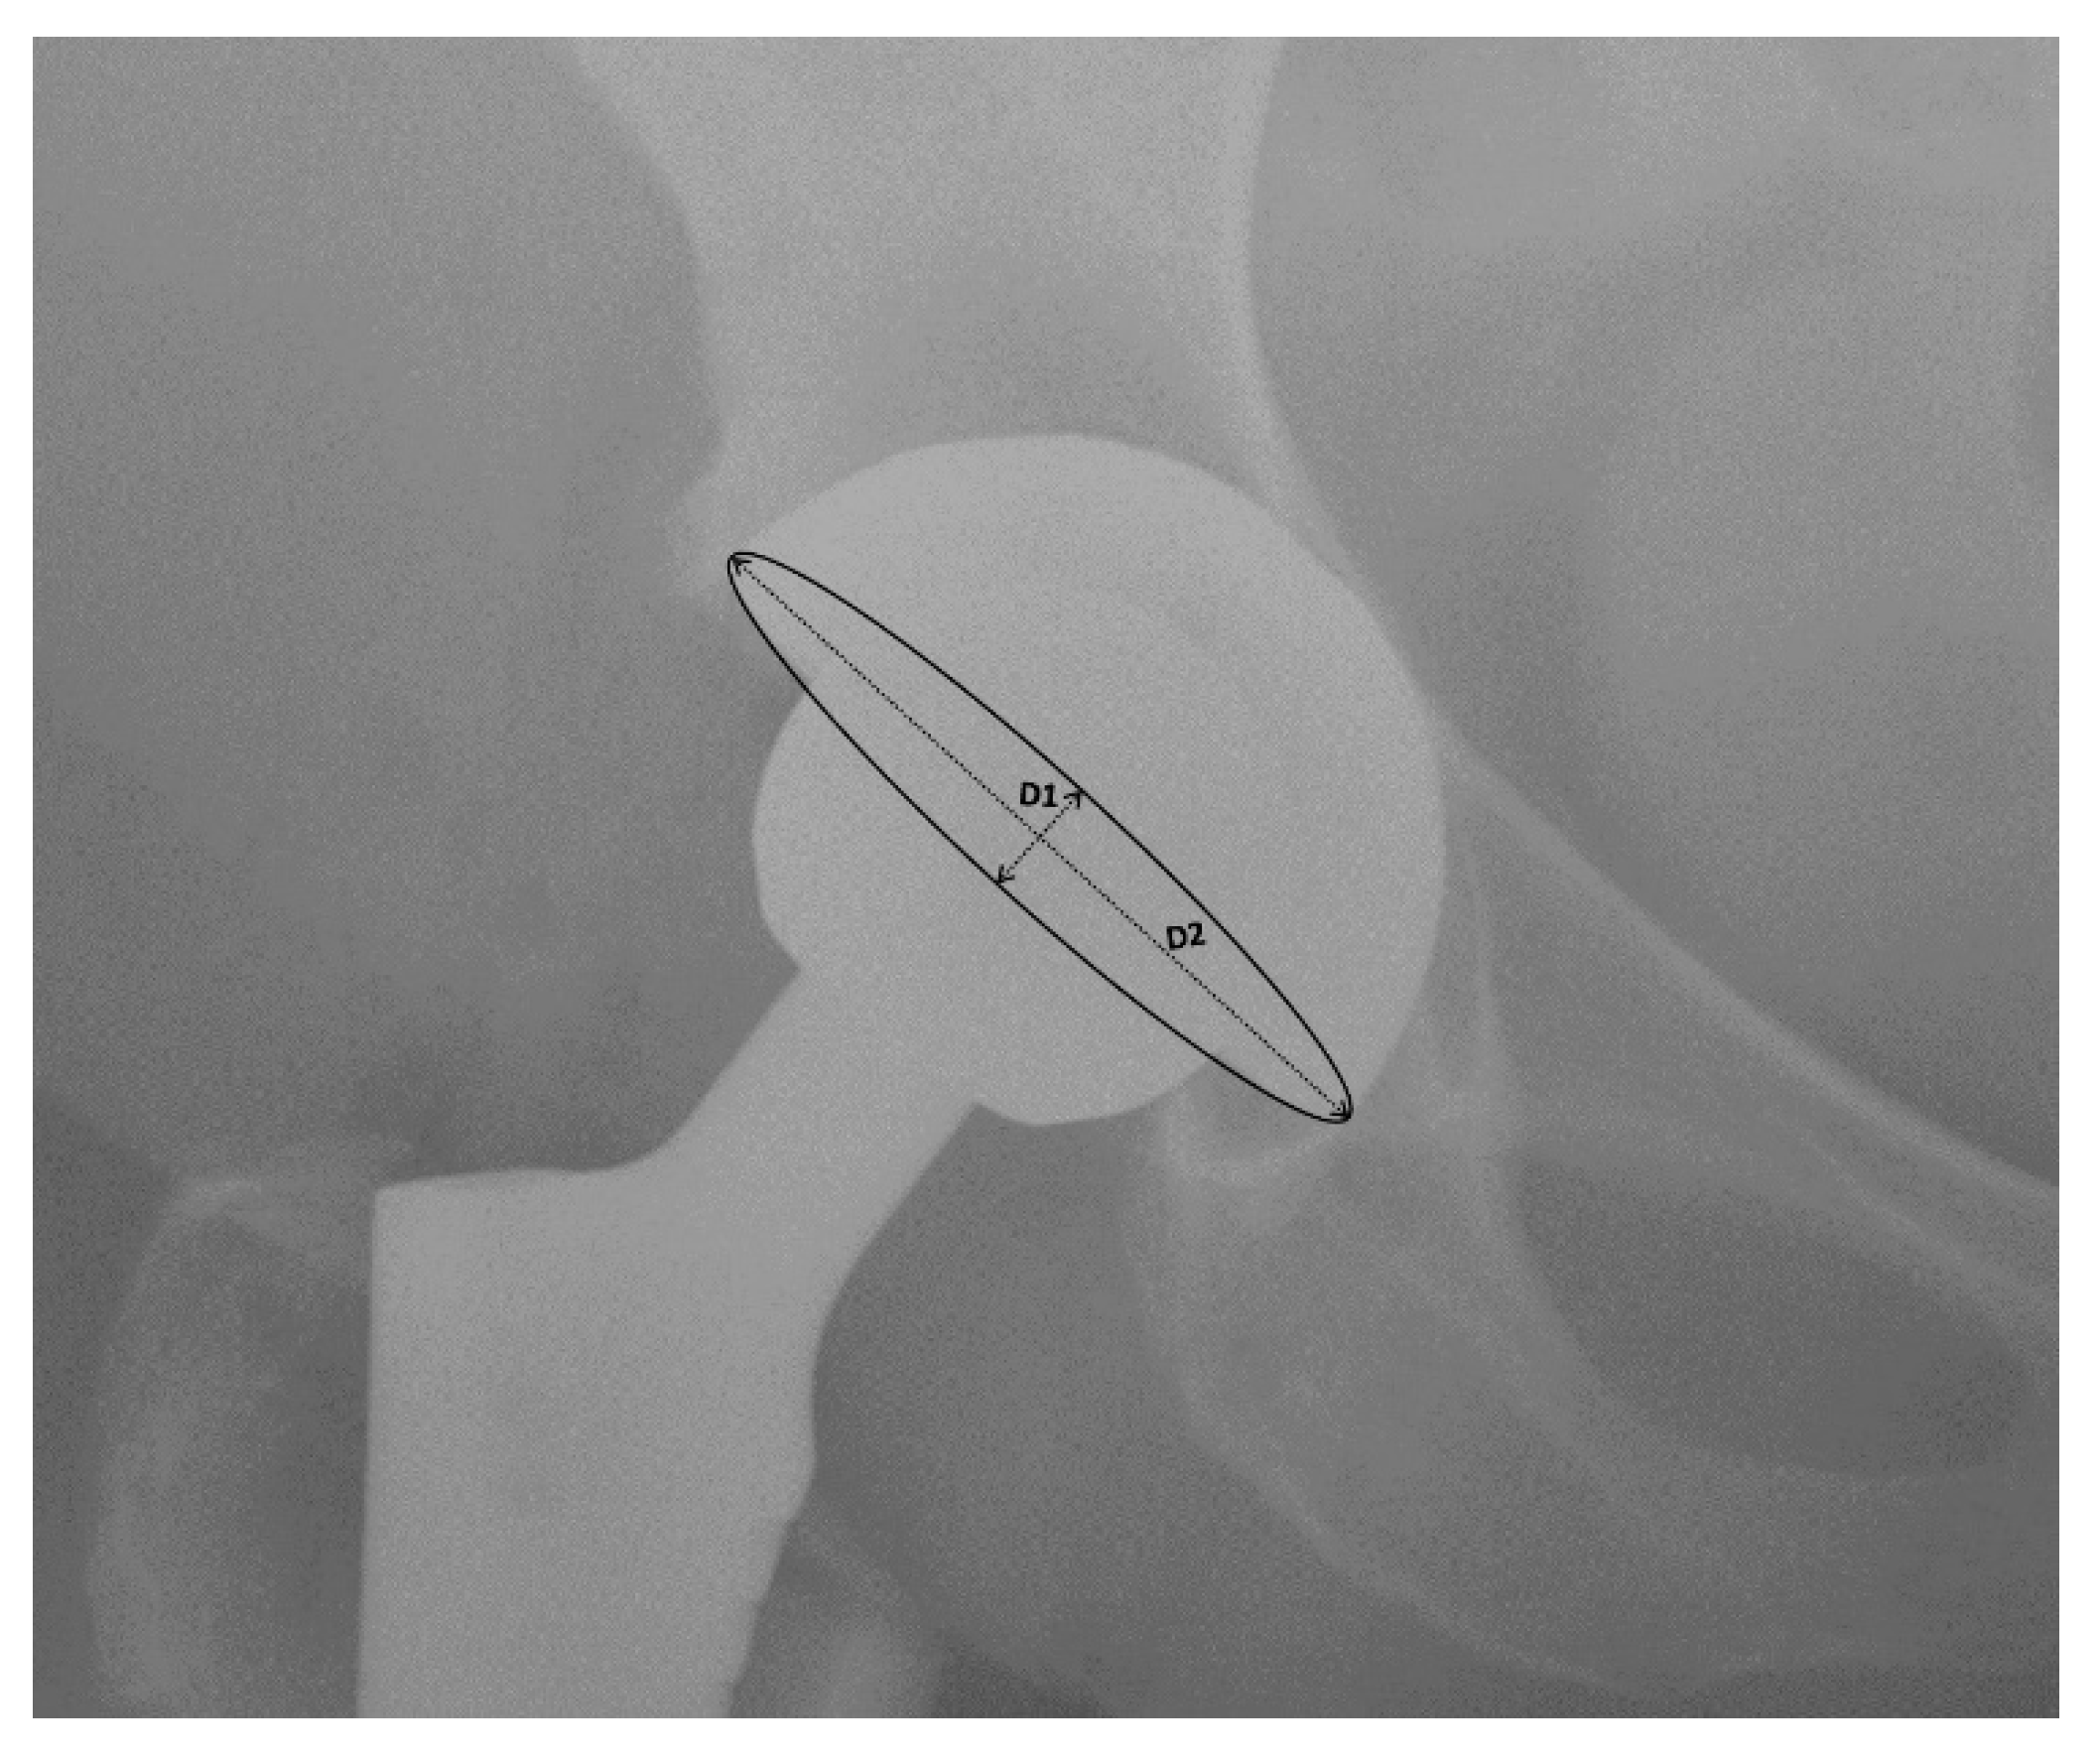

3.4. Mean Radiographic Cup Anteversion

| Cheng [23], 2017 DAA vs. PA | 24.57° | 20.34° | ||

| Taunton [24], 2014 DAA vs. PA | 26° | 29° | ||

| Barret [25], 2013 DAA vs. PLA | 20.1° (SD 5.9°) | 25.8° (SD 8.1°) | ||

| Zhao [26], 2017 DAA vs. PLA | 17.1° | 21.3° | ||

| Taunton [27], 2018 DAA vs. PA | 23° (SD 4°) | 25° (SD 6°) | ||

| Brun [28], 2019 DAA vs. LA | 9.4° (SD 4.8°) | 5.8° (SD 4.3°) |